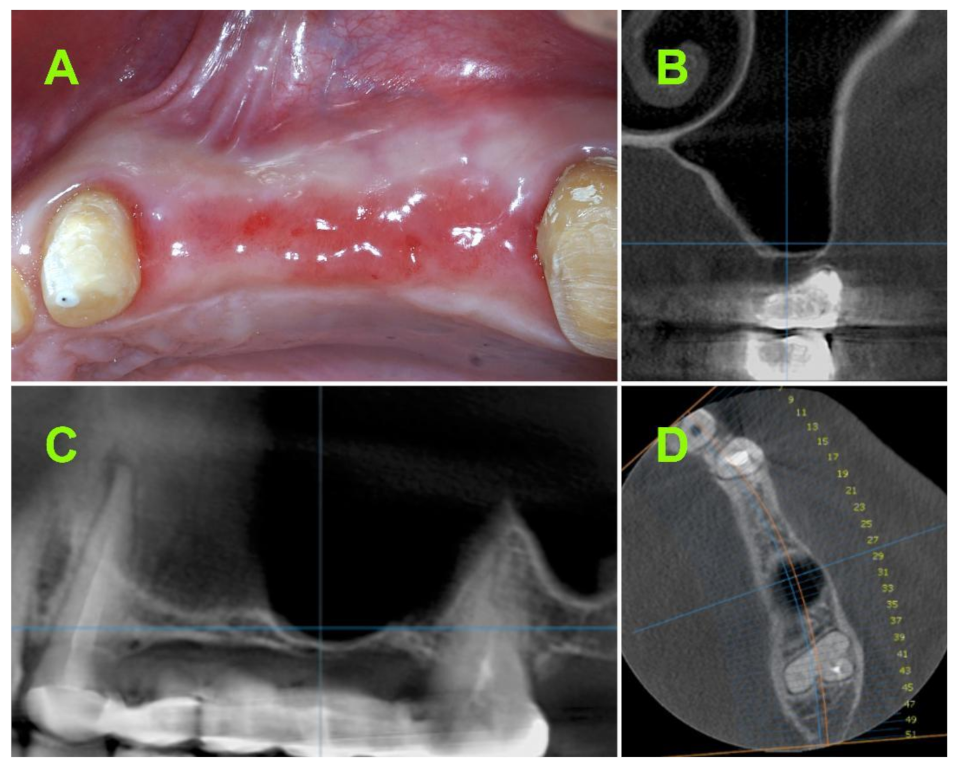

2. Materials and Methods

2.2.1. Pre-Operative CBCT Measurements

2.2.2. Surgical Techniques